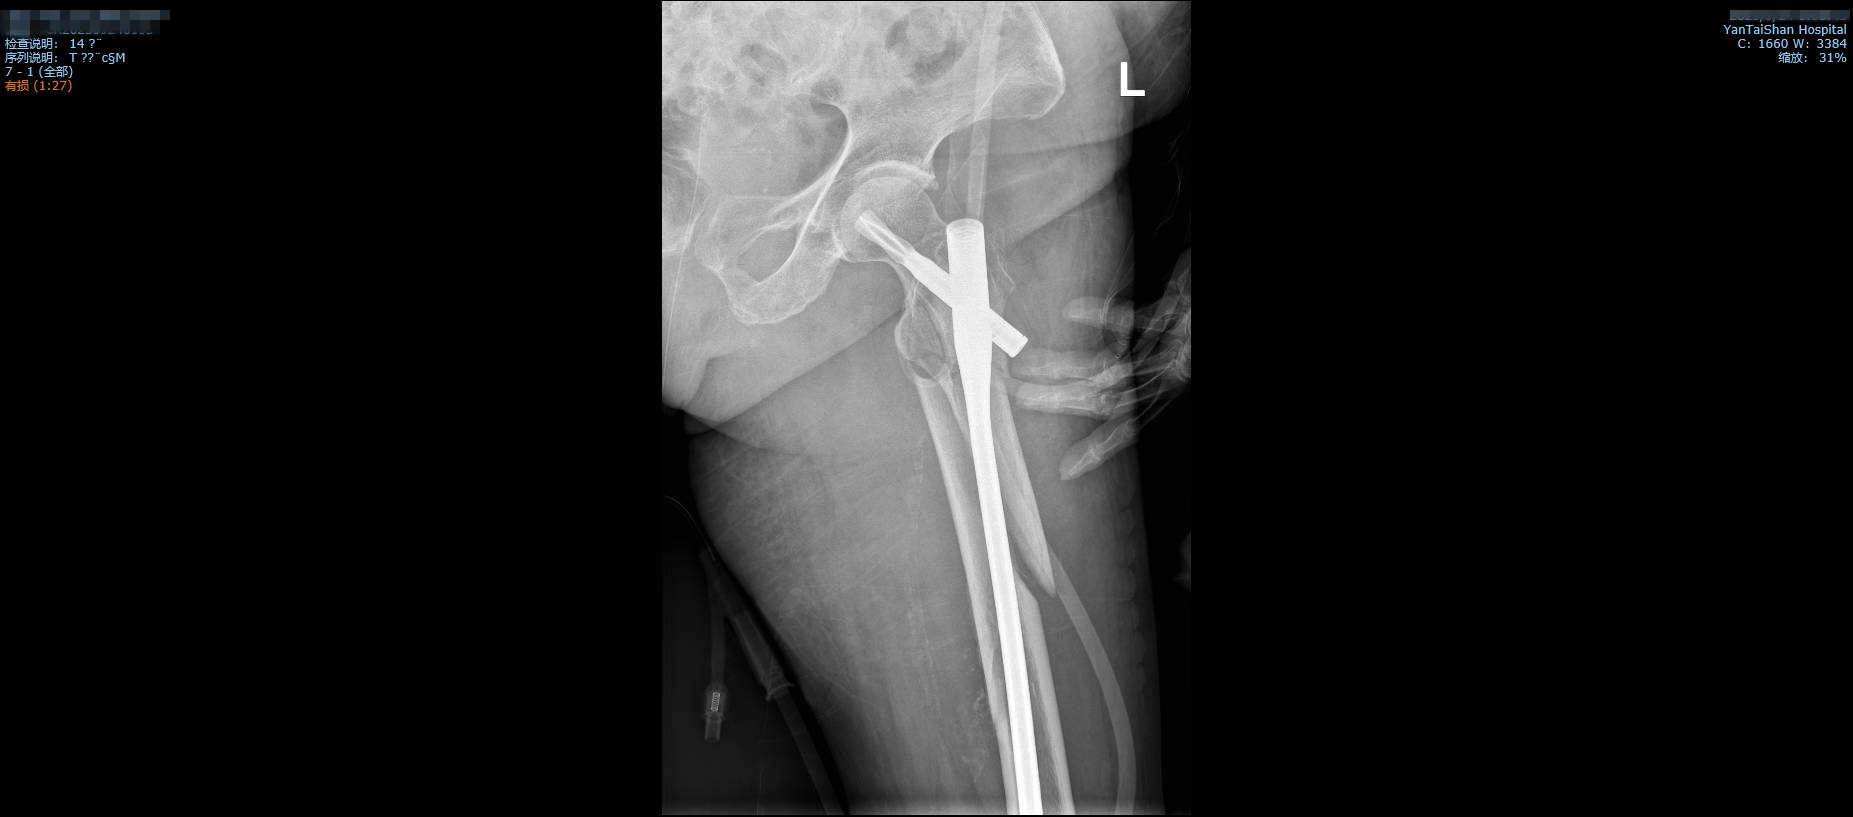

“时间就是生命”,南院骨科尽早为王奶奶安排了手术,这台股骨闭合复位髓内针手术用时只有30分钟,术中出血仅50毫升。

术后影像学检查。